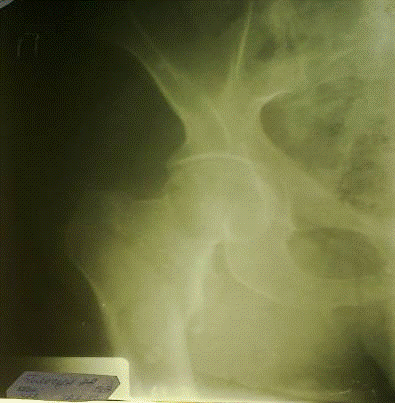

.        Рентгенография костей таза:

От 16.10.2013г.

Заключение: в прямой и боковой проекции правого бедра определяется чрезвертельный перелом правой бедренной кости со смещением фрагментов.

От 22.10.2013г.

Заключение: в прямой и боковой проекции правого бедра определяется чрезвертельный перелом правой бедренной кости в условии скелетного вытяжения. Отломки фиксированы без смещения. Функциональная ось правильная.

Вывод: Динамика рентгенограмм без видимых изменений.